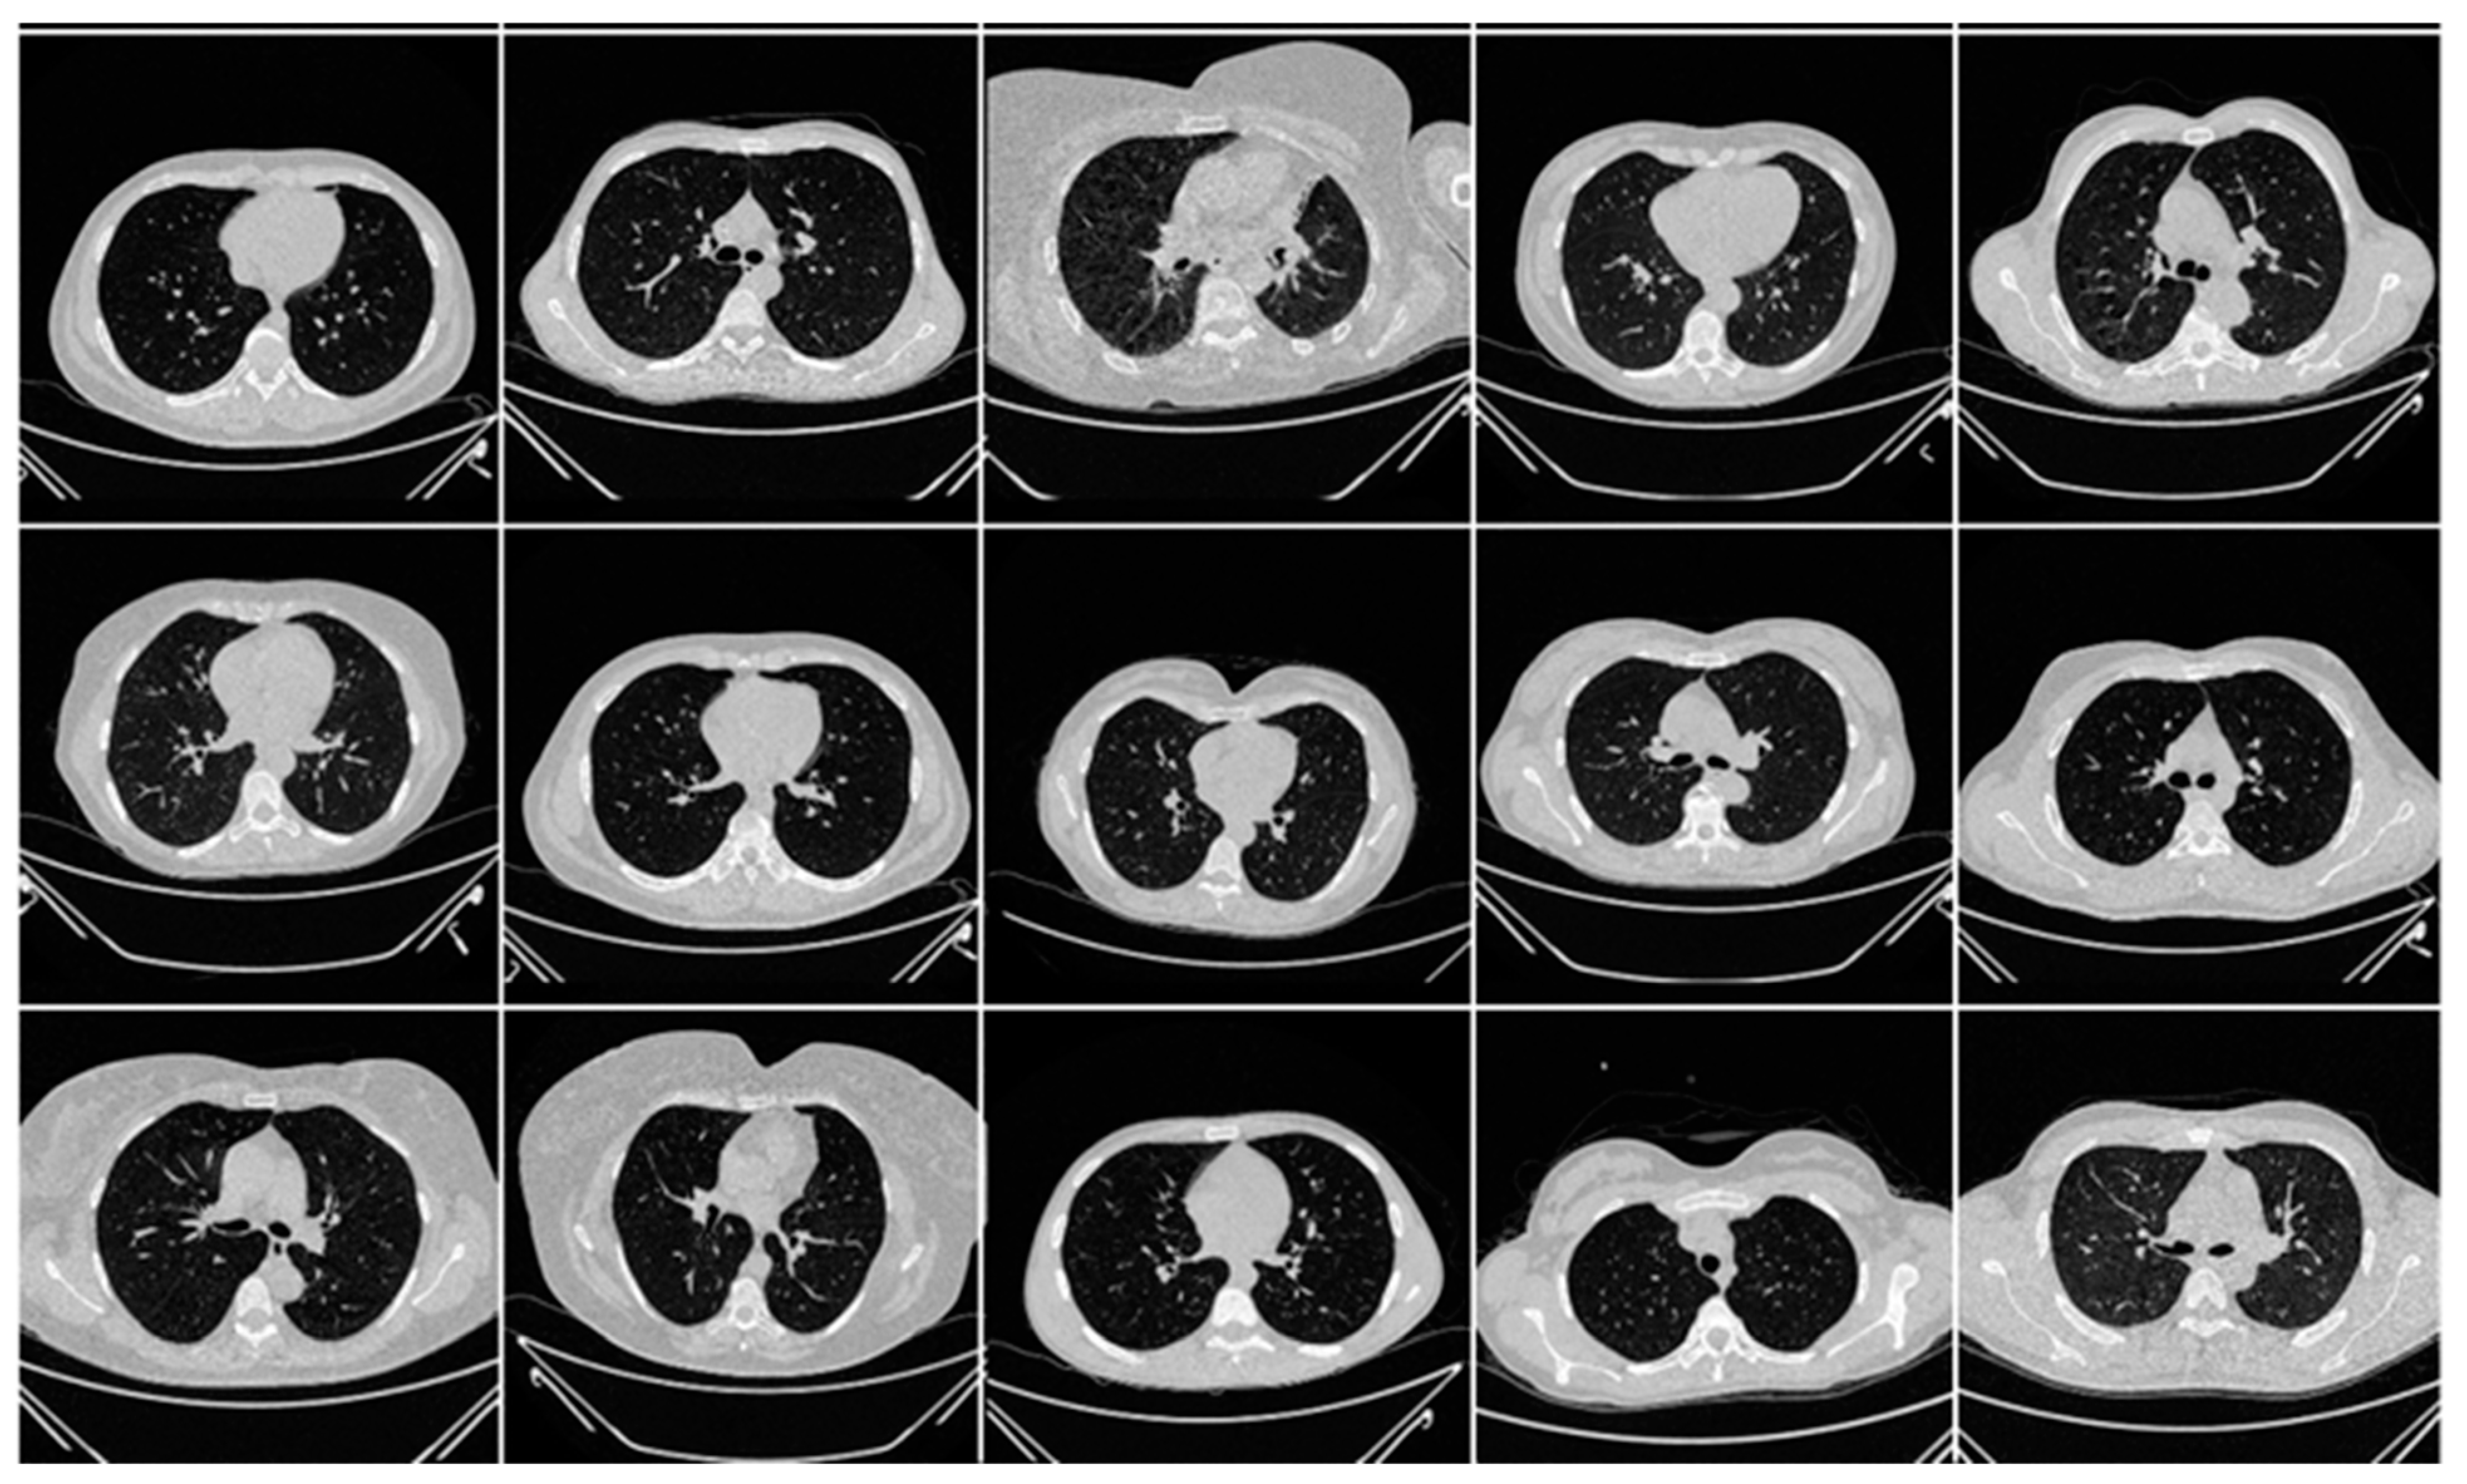

In this research work, we utilized two distinct cohorts from different countries. This dataset has already been validated by radiologists and doctors who are also co-authors in this paper. The first cohort, referred to as the experimental data set, consists of 80 CroMED COVID-19-positive individuals, with 57 males and the remainder female. Sample images are in Figure 1. An RT-PCR test was conducted to confirm the presence of COVID-19 in the selected cohort, with an average value of around 4 for ground-glass opacity (GGO), consolidation, and other opacities. Of the 80 CroMED patients, 83% had a cough, 60% had dyspnea, 50% had hypertension, 8% were smokers, 12% had a sore throat, 15% were diabetic, and 3.7% had COPD. Out of the total cohort, 17 patients were admitted to the intensive care unit (ICU), and 3 patients died due to COVID-19 infection [2,79,80].

Figure 1.

Raw “COVID-19 CT slices” patient images taken from CroMED dataset.

Appendix A includes three figures: Figure A1, Figure A2 and Figure A3. These diagrams are sample images of the dataset. Figure A1 is CroMED (COVID), Figure A2 depicts NovMED (COVID), and Figure A3 shows NovMED (Control).

Raw “COVID-19 CT slices” taken from CroMED Dataset.